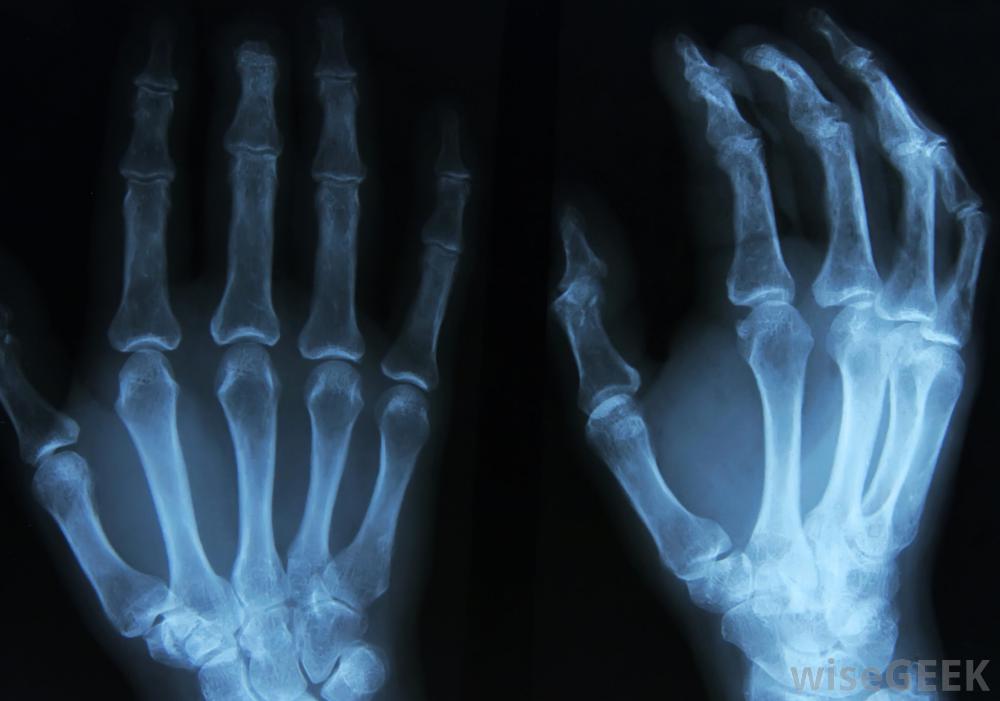

什么是Bouchard節點(Bouchard's Nodes)?

Bouchard~s結節是指或腳趾近端指間關節或中間關節擴大和扭曲的骨、軟骨或膠狀囊腫的生長物。這些結節使關節呈現腫脹的外觀,其周長比手指其他部位大得多,是骨關節炎的早期癥狀。其名稱來自查爾斯·約瑟夫·布查德博士是19世紀末法國病理學家,他對關節炎進行了廣泛的研究。就像赫伯登氏結影響手指和腳趾末端的最小關節一樣,Bouchard淋巴結可能不會疼痛,但通常伴隨著關節活動的減少溫熱的融化蠟可以用來舒緩腫脹的關節和關節炎的手骨關節炎,骨關節炎診斷骨關節炎,尤其是在病情嚴重之前的早期階段。大多數骨關節炎檢查需要實驗室檢查,如X光片或血液檢查,但任何醫生都可以通過簡單的觀察快速識別出Bouchard淋巴結。在確定骨關節炎之后,醫生可能會決定使用一個或多個實驗室檢查來發現病情的嚴重程度骨關節炎癥狀,包括疼痛、腫脹和僵硬Bouchard淋巴結的原因目前還不完全清楚,但遺傳學確實起著重要作用,如果父母或其他親屬有這種結節,患者更可能發生這些結節。大多數研究人員認為,這些結節是由軟骨和骨頭的突出物引起的,稱為骨贅,通常發生在關節惡化的部位,并與骨關節炎的其他癥狀有關。然而,在這一點上的一致意見并不普遍,而且Bouchard淋巴結的來源也是一個爭議點。大多數Bouchard和#039;s結節的檢查將包括X光片。骨關節炎是不可治愈的,但有一些治療方法。這種治療側重于保持活動性,盡量減少關節變形和處理疼痛。在早期階段,非處方治療可能已經足夠了,但隨著病情的發展,非處方治療可能不夠充分。食物補充或改變飲食也可能是推薦的。Bouchard淋巴結的存在通常可以使早期診斷,并可提示早期反應,使患者能夠在不采取更嚴重措施的情況下控制關節炎。Bouchard';s淋巴結通常表示存在骨關節炎隨著病情的發展,可能會考慮使用處方藥,根據關節炎的嚴重程度,可能需要進行手術。在某些情況下,注射可的松可以減輕炎癥和減輕疼痛。手術選擇包括去除骨刺、關節融合甚至關節置換。患者應咨詢由醫學專家討論最佳選擇。嚴重的骨關節炎可能會抑制患者獨立站立的能力Bouchard淋巴結是由軟骨和骨的突出引起的,稱為骨贅,這與骨關節炎的其他癥狀有關。